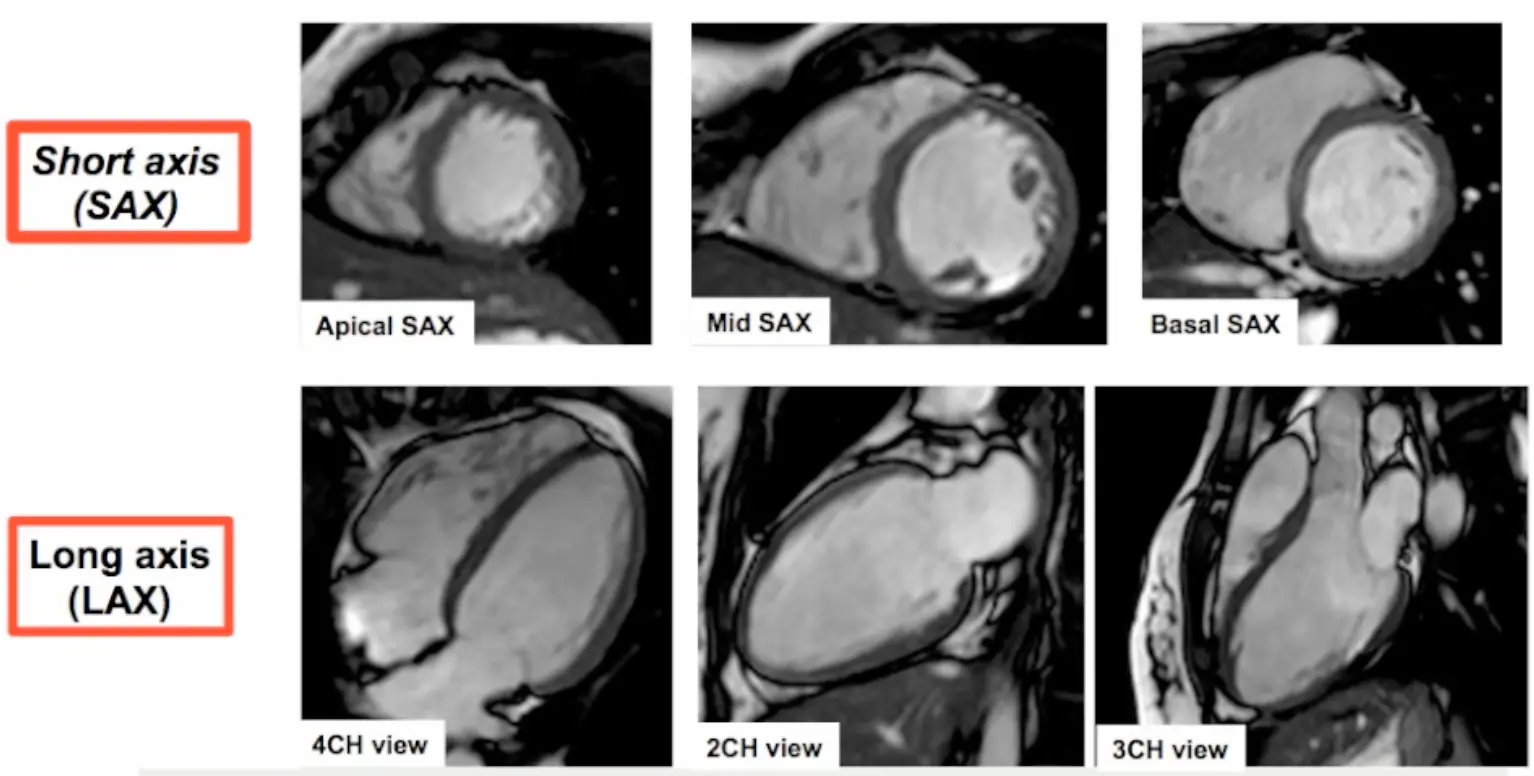

Basic Cardiac Views

How CMR Images Are Obtained

- Step 2. Short axis (SAX) stack acquisition

- The SAX stack is acquired using cuts that are perpendicular to the VLA and HLA views. The SAX stack acquisition has the advantage of minimizing oblique cuts through the myocardium, which may provide a false impression of regional wma.

- 5-slice LV slicing is conducted using end-systole

- Step 3. Long axis (LAX) views acquisition

- 4CH view

- 3CH view

- 2CH view